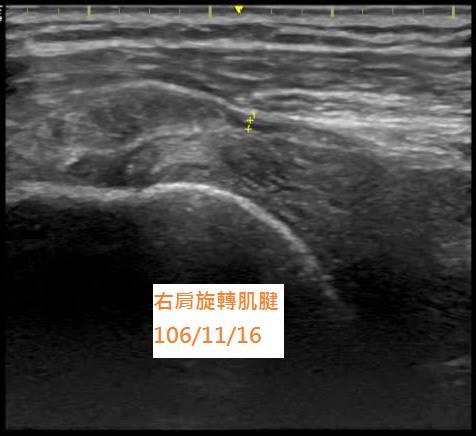

後來經由其他醫師介紹來到本院就診,在高解析度超音波詳細檢查後,發現她的肩部旋轉肌腱有將近50%的撕裂傷(圖一),這麼大一個傷口在肩膀裡,難怪她疼痛不已。

(圖一:超音波顯示旋轉肌腱局部撕裂傷)